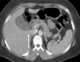

Rectal perforation

Rectal foreign bodies are large foreign items found in the rectum that can be assumed to have been inserted through the anus, rather than reaching the rectum via the mouth and gastrointestinal tract. It can be of clinical relevance if the patient cannot remove it the way they intended. [Source: Wikipedia ]